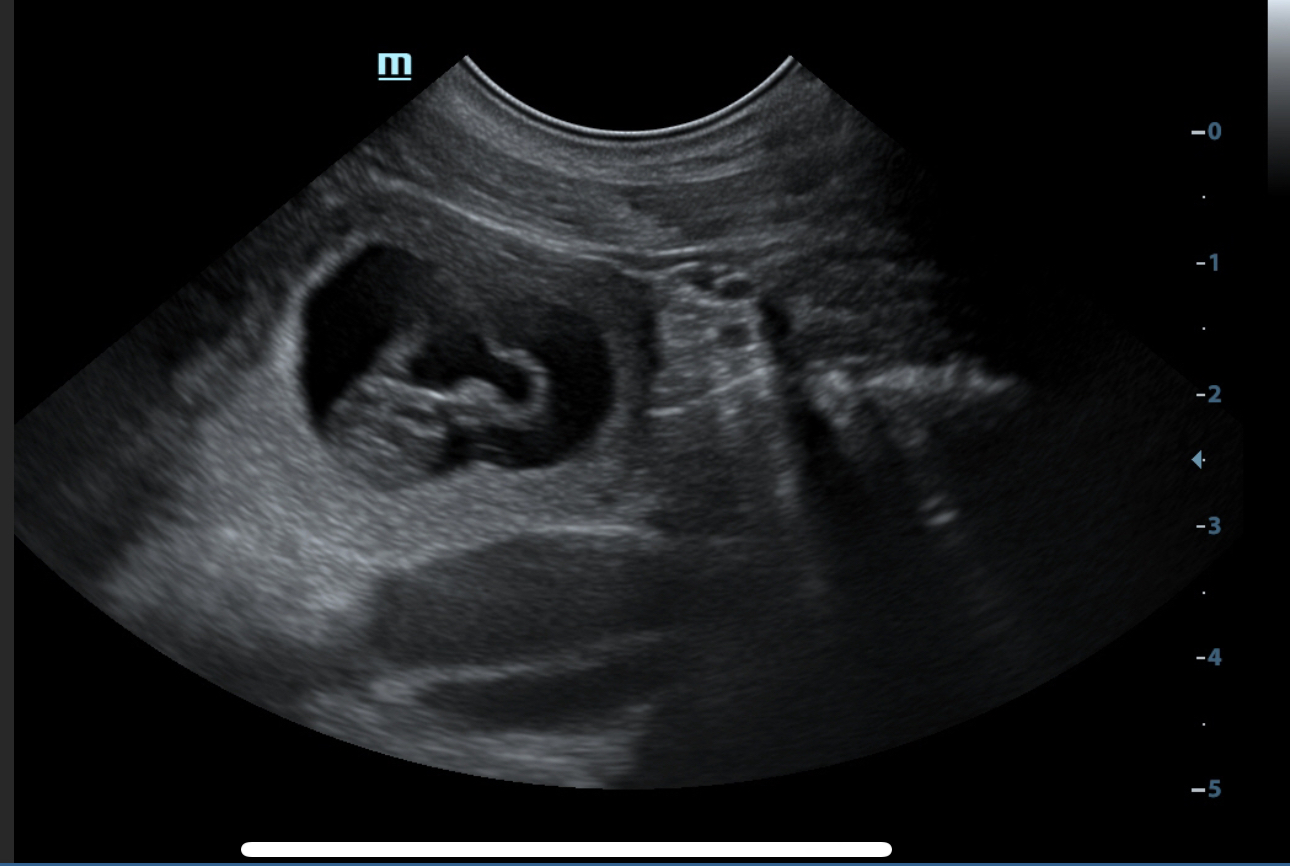

Der P-Wurf ist angekommen, wir freuen uns über 4 Jungs und ein Mädel.